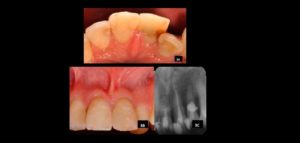

132 – Tratamiento de la reabsorción radicular interna idiopática perforante: controles radiográficos

La reabsorción radicular interna (RRI) es una afección inflamatoria que resulta en la destrucción progresiva de la dentina intra-radicular a lo largo de los tercios